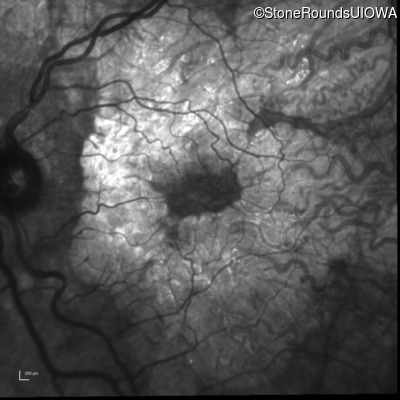

Infrared Fundus Photograph - Right - 20/20 -2

Exemplar

Infrared Fundus Photograph - Left - 20/25